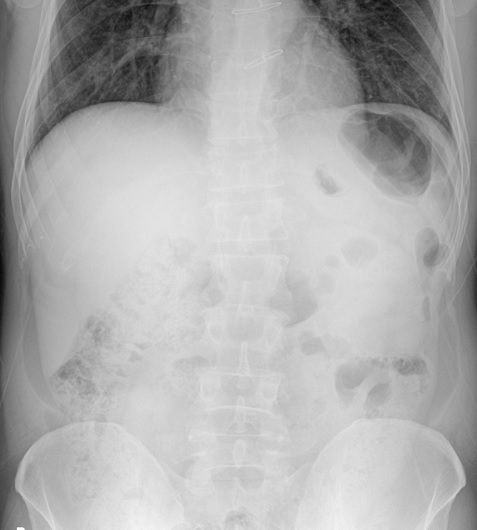

Bệnh nhân nam,54 tuổi nhập viện vì bị một cây gỗ đập vào vùng bụng dưới rốn cách nhập viện 5 giờ. Bệnh nhân đau nhiều vùng hố chậu trái, không sốt, không buồn nôn hay nôn mửa. Khám lâm sàng thấy bụng mềm, không có vết bầm tím trên thành bụng, hố chậu phải mềm hoàn toàn, ấn đau 1 vùng khoảng 10× 10cm vùng hố chậu trái, phản ứng thành bụng (±), tiểu tự chủ vàng trong. Xét nghiệm cận lâm sàng bình thường ngoại trừ bạch cầu tăng nhẹ 10.77 G/L neurophile  83%. X quang bụng đứng không có liềm hơi dưới cơ hoành (Hình 1), không có mức hơi dịch. Siêu âm bụng không có hơi tự do, không có dịch ổ phúc mạc.

Hình 1. X quang bụng khi vào viện không có liềm

hơi dưới cơ hoành